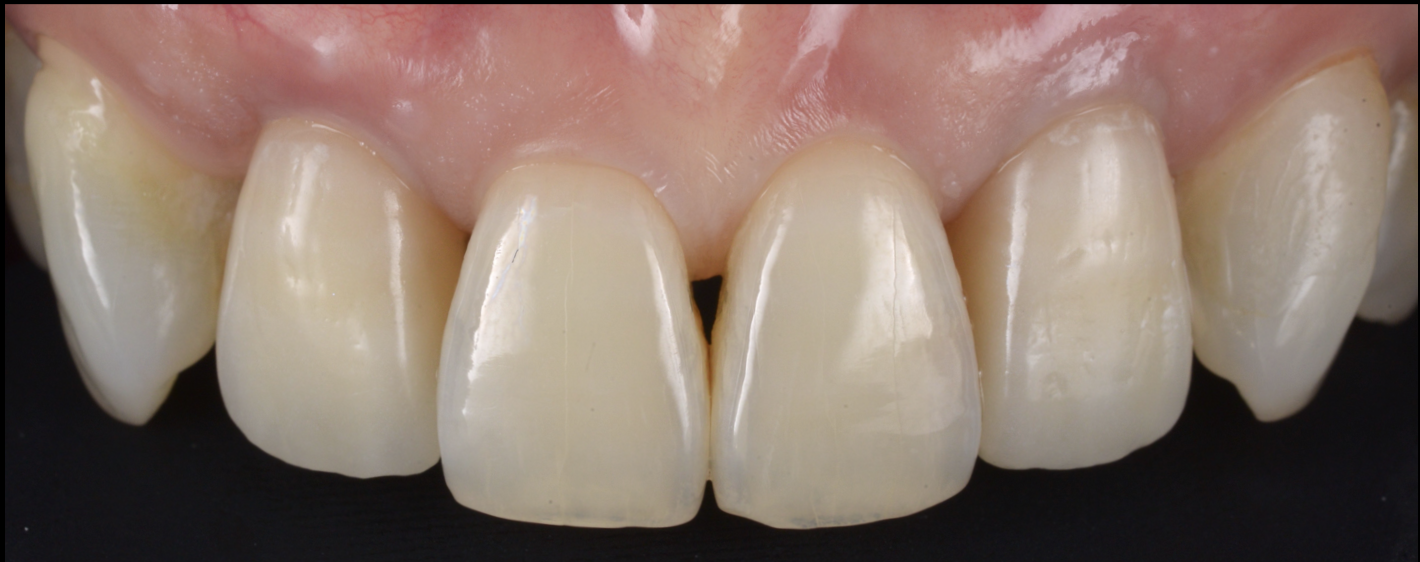

治療後

歯の保存、嚢胞の摘出、審美的改善